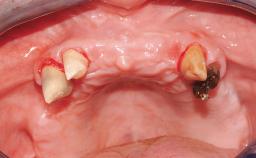

Immediate Loading of Six Implants in the Maxilla and Final Restoration with a Full-Arch CAD/CAM Zirconia FDP

A 63-year-old male patient was referred for a consultation and treatment of partial edentulism in the maxilla. The patient presented with residual anterior teeth and declined a partial removable prosthesis. He reported that the maxillary posterior teeth had been extracted due to mobility and periodontal disease two months before the consultation. The patient’s chief complaint was that his residual maxillary teeth were mobile and that he was unable to chew. The patient’s desire was a stable and comfortable fixed maxillary rehabilitation. The patient was a light smoker (fewer than 10 cigarettes/ day), and his medical history was without significant findings. He was not on any regular medication at the time of consultation. The extraoral examination revealed a normal physiognomy with a correct distribution of the facial thirds. The patient presented a low lip line, and the transition line between teeth and soft tissues was not exposed during a forced smile.

# of Implants 6

Type of Implants One-Piece